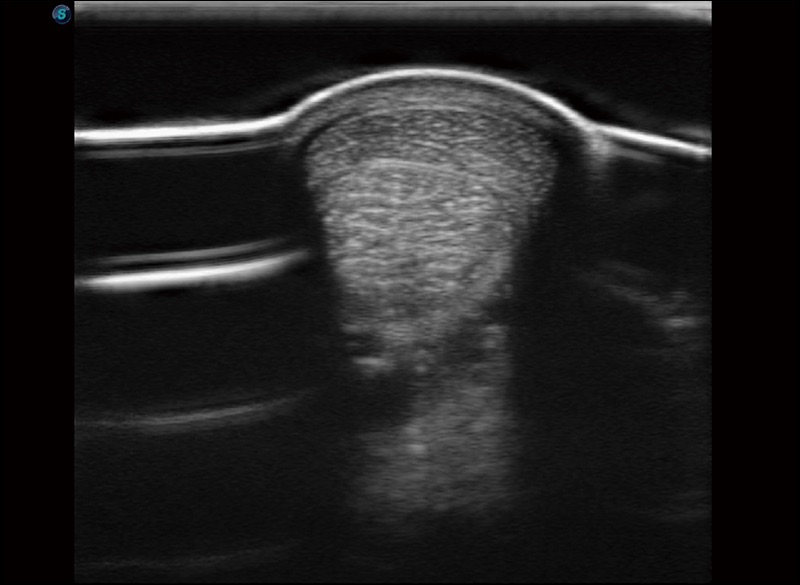

扩展成像

支持线阵和凸阵探头,一键操作即可获得更宽的图像视野

实时宽景成像

可实时观察感兴趣区域和病变位置